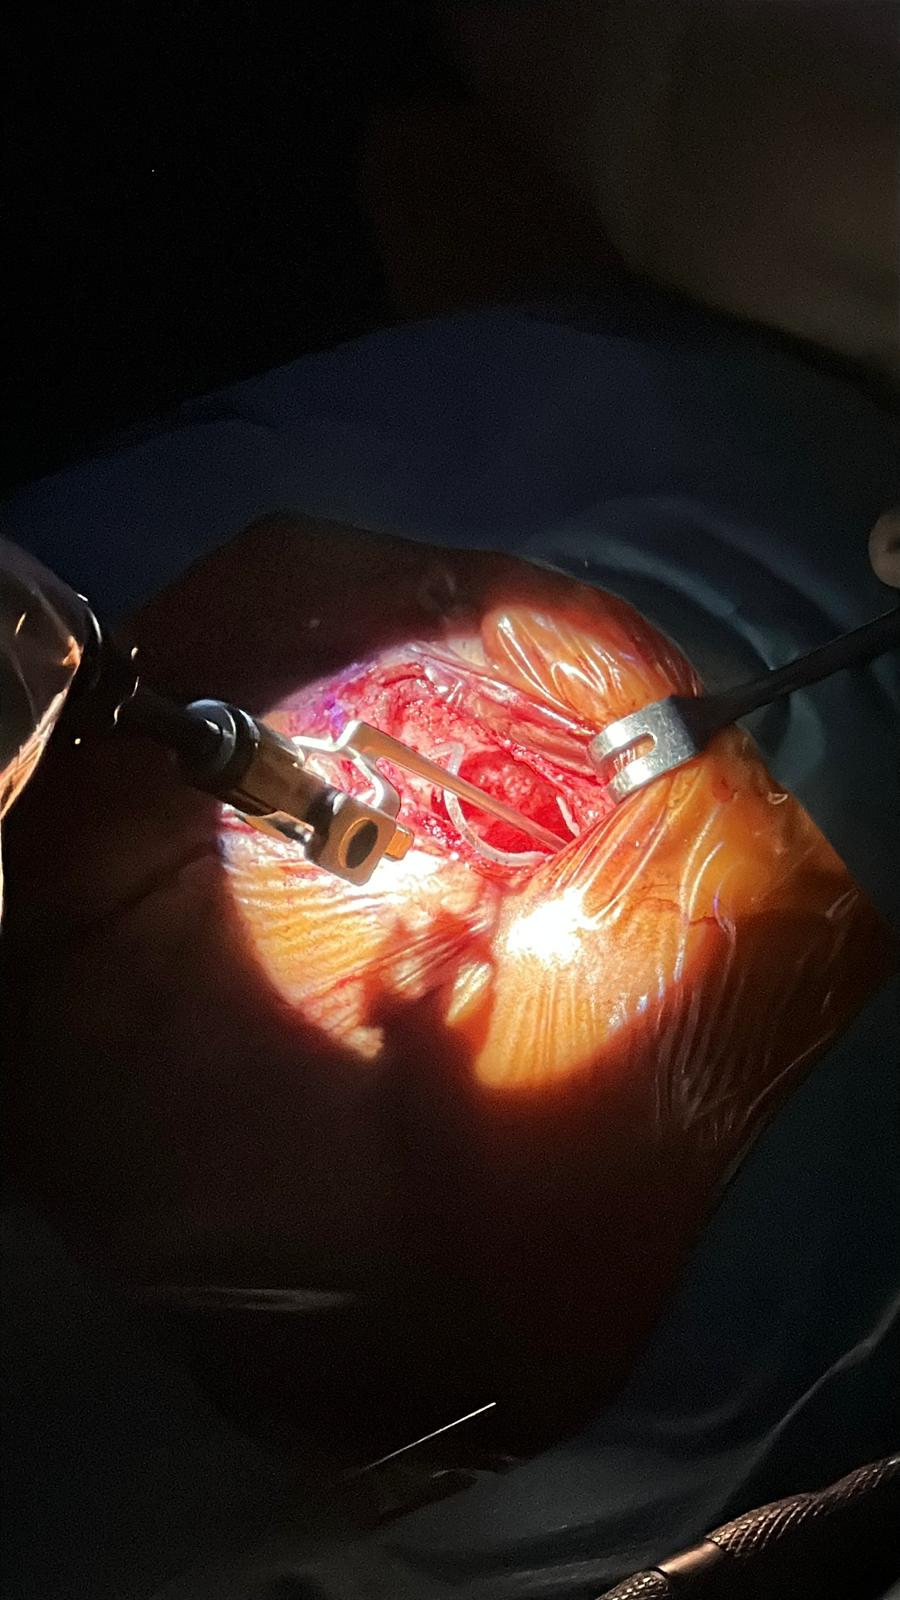

Otodrive este un sistem robotic portabil, dezvoltat de companiile Cascination și MED-EL, conceput pentru a oferi control maxim în etapa cea mai delicată a implantării cohleare: inserția electrodului în cohlee. Compact și ușor de transportat, robotul poate fi instalat rapid în sala de operație și se integrează fără dificultate în fluxul chirurgical obișnuit.

În cadrul intervenției s-a utilizat implantul Synchrony 2 (MED-EL), cu un porte-electrod Flex Standard, ales pentru caracteristicile sale atraumatice și compatibilitatea perfectă cu sistemul robotic.

Robotul Otodrive permite o viteză de inserție reglabilă între 0,1 și 1 mm/s, oferind o manevră stabilă și repetabilă, independent de variațiile umane inevitabile în timpul gestului operator.